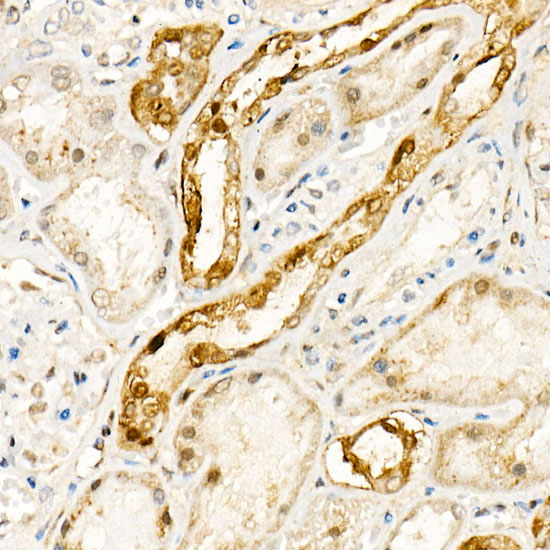

ApplicationWB, IHC, ELISA; Recommended dilution: WB 1:500 - 1:1000, IHC 1:50 - 1:200, ELISA - Recommended starting concentration is 1 μg/mL. Please optimize the concentration based on your specific assay requirements.